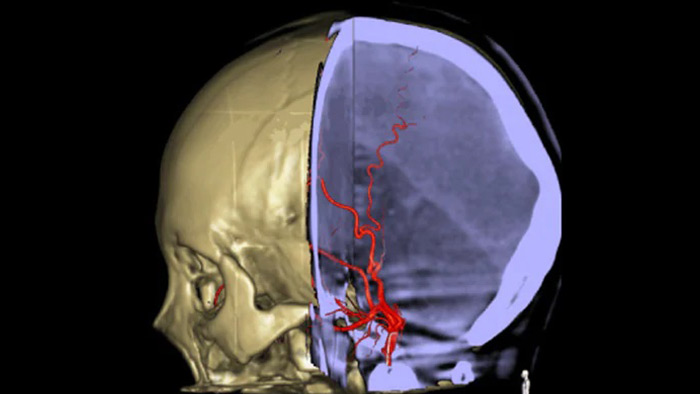

Drei SmartCT Aufnahmen

CT-artige Darstellung

SmartCT Soft Tissue generiert eine CT-artige Darstellung des Weichgewebes und erleichtert die Schlaganfalldiagnose auf drei Arten: Ein kontrastmittelfreier Scan hilft bei der Erkennung früher ischämischer Veränderungen. Ein Scan der frühen Phase hilft bei der Identifizierung des proximalen Verschlusses. Ein kontrastmittelverstärkter Scan der Spätphase unterstützt die Erkennung von Kollateralen.

SmartCT Vaso IV

Überprüfung der Position und Länge eines Gerinnsels

Dank der periprozeduralen Darstellung von Aspekten distaler Gefäße bei ischämischen Schlaganfällen ermöglicht SmartCT Vaso den Blick hinter das Gerinnsel. SmartCT Vaso ist eine Erfassungstechnik, die auf einem Cone-Beam-CT-Scan in Kombination mit einer intraarteriellen Kontrastmittelinjektion basiert. Durch retrograde Füllung werden die Gefäßstrukturen vor und hinter dem Gerinnsel sichtbar. Die SmartCT Vaso 3D Roadmap kann zur Darstellung von Instrumenten zur Entfernung von Gerinnseln verwendet werden.